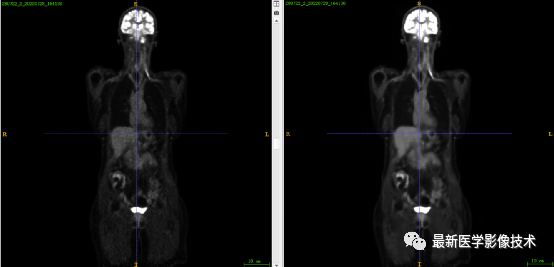

7.2、低剂量4重建结果

第一张是低剂量4的PET图像,第二张是full剂量PET图像,第三张是网络重建的PET图像。